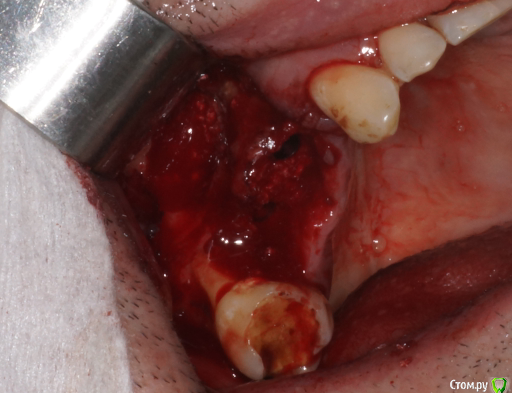

Пришел пациент с вопросом о 1.5. Поговорили о варианте одномоментного всего. Ушел на КТ. Принес такое.

Я сначала решил, что в пазухе новообразование. Посмотрев внимательнее подумал что корень. Оказалось нечто среднее - недоформировавшийся корень, вросший в стенки пазухи.

В день вмешательства обрадовала ассистент - оказывается заказ "открытый синус лифт" еще не предполагает заказа на комплект гладилок. Сетевые клиники такие сетевые. Пришлось дедовским способом - турбинка, серповидная и распатор.

Ах да, забыл совсем. Удалил по ходу действия 1.8, обратите внимание на пазуху по КТ - септа в проекции 1.7 так удачно отделила отекшую слизистую от области синуса)